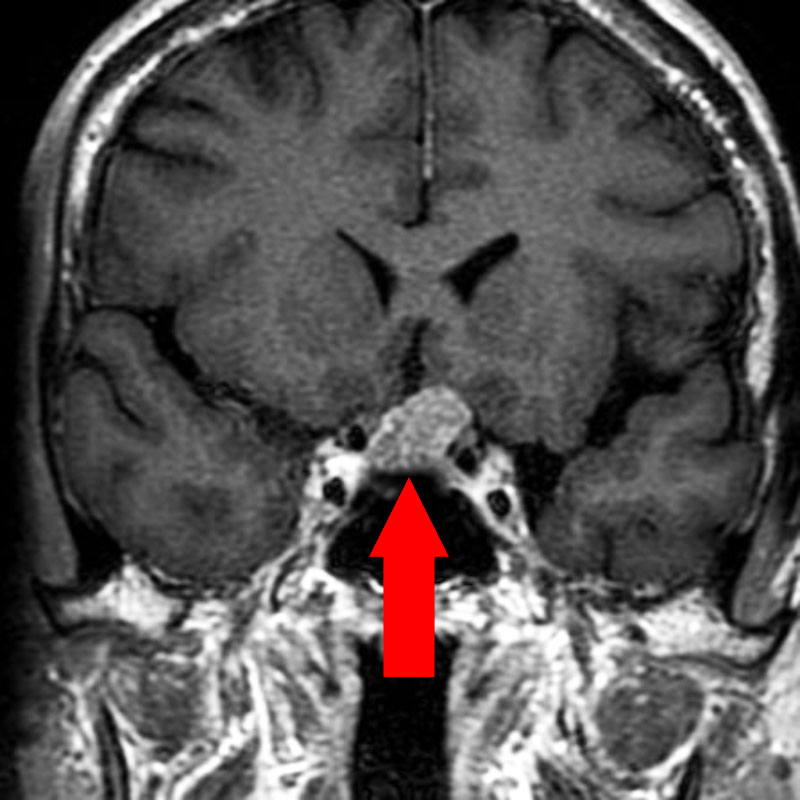

下垂体腫瘍

頭蓋内腫瘍摘出術

No.’22_98 手術前1

No.’22_98 手術前2